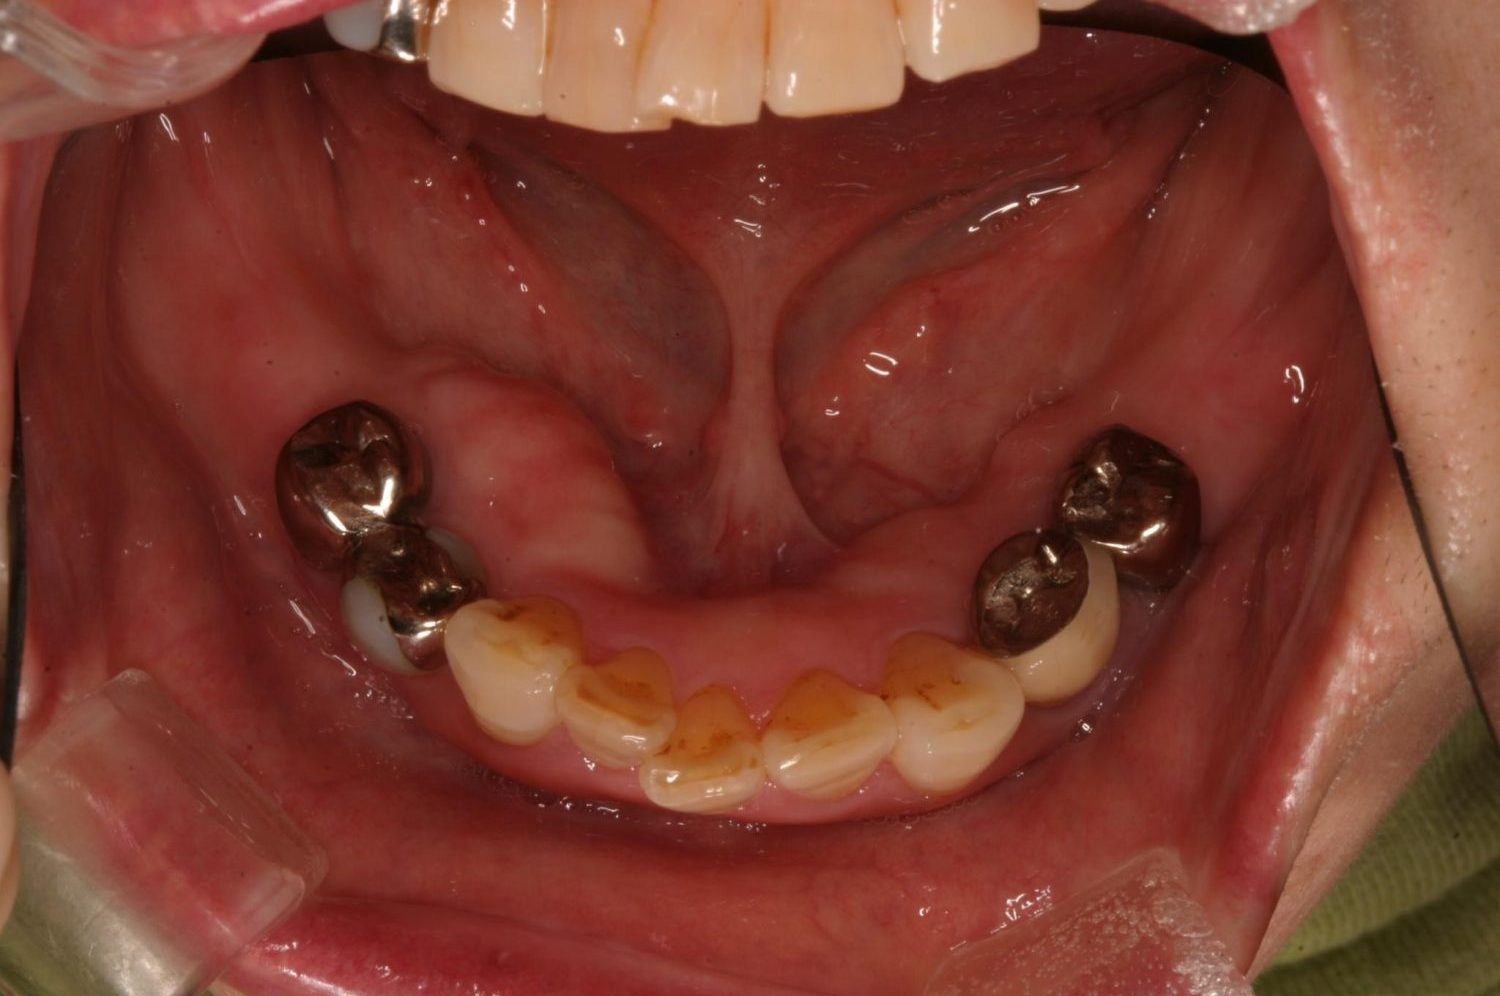

インプラント治療の症例紹介③

Before

After

主訴

むし歯の治療

治療内容

保存不可能な歯の抜歯

下顎にインプラント埋入し咬合再構成

治療費

2,688,400円(税込)

治療期間

14か月

治療回数

21回

想定されたリスク

※上部構造の形態が複雑になるため清掃が難しくなる。インプラント周囲炎の恐れがありました。

多数歯う蝕および多数歯欠損による咬合崩壊、保存不可能な歯の抜歯により上下無歯顎に。下顎に6本インプラント埋入する事で咬合再構成を行った。